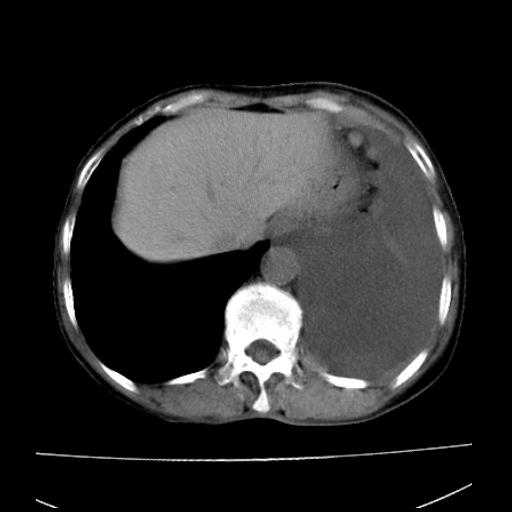

以下是引用随光逐影在2010-3-24 19:15:00的发言:[br]结合病史,考虑双肺及纵隔淋巴结多发转移、左侧胸膜转移并左侧大量胸水,左下肺膨胀不全。

以下是引用zxl51642在2010-3-24 18:49:00的发言:[br]结合乳腺癌术后病史,考虑双肺及纵隔淋巴结多发转移、左侧胸膜转移并左侧大量胸水、左下肺膨胀不全。